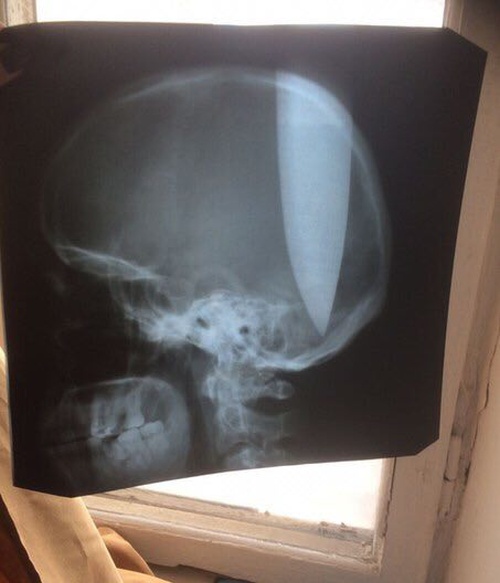

Полицейские, приехавшие по вызову в Ростове, были шокированы увиденным, впрочем, как и медики. Полицию вызвали случайные прохожие, которые увидели мужчину, сидящего на траве, с ножом в голове. Все дело в том, что мужчина воткнул в свою голову нож, который прошел сквозь весь череп, но пострадавший находился в сознании. По его словам, он сделал это, чтобы "голова подышала"... Не для впечатлительных.

Мужчину прооперировали, и он уже идет на поправку. Этот случай стал действительно уникальным, ведь он вогнал нож ровно между полушариями, поэтому мозг не получил значительных повреждений. По некоторым источникам, пострадавший состоит на психиатрическом учёте.